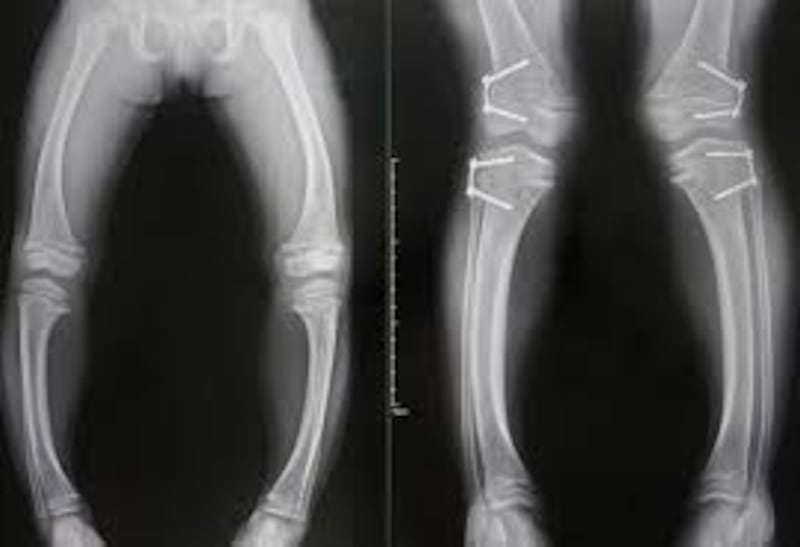

“En niños, la enfermedad se manifiesta principalmente con piernas arqueadas cuando comienzan a caminar, entre los 12 y 24 meses de edad. En adultos, puede derivar en osteomalacia, dolor, rigidez articular y mayor riesgo de fracturas”, agregó.

Vázquez detalló que en etapa pediátrica, la hipofosfatemia puede provocar raquitismo, una alteración visible en radiografías donde el hueso presenta una estructura debilitada.

Cuando el crecimiento óseo concluye en la adultez, el cuadro evoluciona hacia osteomalacia, que se traduce en fragilidad estructural y posibles fracturas.